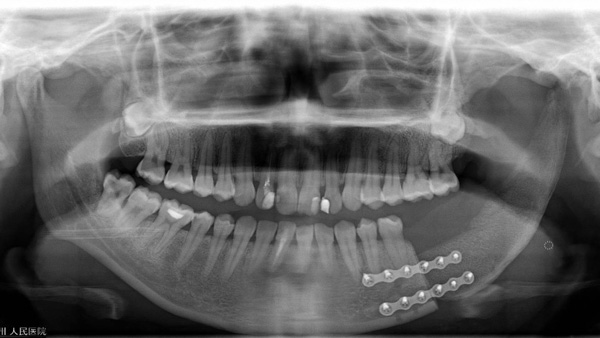

手術當天,口腔科手術團隊首先按照術前設計并3D模擬的截骨導板對下頜骨及腫瘤精準切除;再根據術前設計的髂骨截骨導板精準取骨和精準切割塑形拼接,后把移植骨的動脈和靜脈在顯微鏡下吻合到頸部的動脈和靜脈血管上,重建血循環,恢復功能,經過十多個小時的努力,終于圓滿完成了下頜骨缺損重建。

該例復雜的髂骨重建下頜骨手術得以成功實施,是柳州市人民醫院口腔科頜面外科團隊高超技術實力的證明,通過先進的輔助手段,讓很多傳統手術的方式發生了改變,不僅能為患者“治病”,還能滿足患者在頜面功能保留和美觀方面的需求,讓患者能夠高質量回歸正常生活。